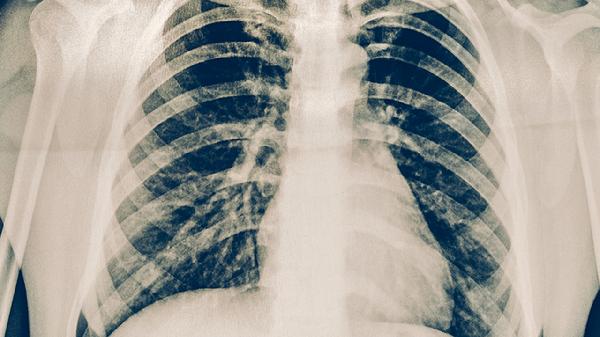

肺结核盗汗主要表现为夜间睡眠中大量出汗,常伴随低热、乏力等症状。盗汗可能与结核分枝杆菌感染引起的免疫反应、体温调节异常等因素有关,需结合痰涂片、胸部影像学等检查确诊。